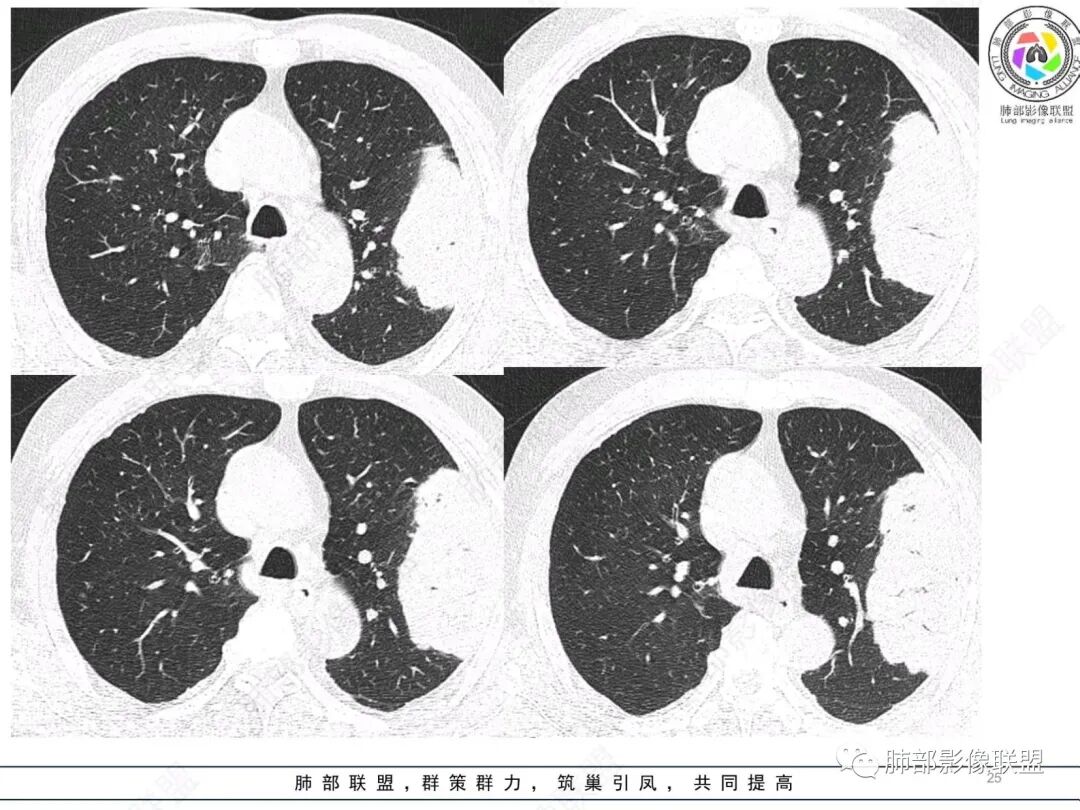

左肺上叶大肿块,膨胀性生长,边界清,密度较低,见部分坏死区,强化弱,肿块见支气管充气V扩张征,分布僵直,枯树枝特点,另一个重要特点血管造影征,淋巴瘤,肿块长轴与胸膜平行,与隐球菌鉴别,隐球荚膜抗原检查,明确诊断经皮肺穿刺。另胸膜钙化(问诊既往有无患胸膜炎病史)。

左肺上叶胸膜下肿块,宽基底与胸膜相连,跨叶裂,边缘清晰膨隆,其内支气管充气,部分扩张、僵直,无明显强化,血管造影征,考虑淋巴瘤,鉴别腺癌

左肺胸膜下巨大占位,跨叶裂,宽基底与胸膜相连,胸膜钙化,平扫密度较低,强化不明显,可见内部血管显影,支气管充气征和扩张,考虑为恶性,倾向于淋巴瘤

放射线:

左肺上叶胸膜下肿块,膨胀性生长,边界清晰,密度不均部分坏死,未见强化,病灶内支气管迂曲扩张,病灶长轴与胸膜平行,胸膜下脂肪间隙存在,胸膜钙化,考虑放线菌?毛霉?鉴别淋巴瘤

支持淋巴瘤,左上肺大肿块,有分叶,边缘光整,病灶内密度不均,可见支气管扩张征,增强后可见血管影征。周围肺野清晰。

左肺上叶肿块,宽基底与胸膜相连,跨叶裂,边缘清晰膨隆,可见小分叶,其内支气管充气,部分扩张、僵直,呈枯枝征,支气管达边征,增强无明显强化,可见血管造影征,考虑恶性病变,淋巴瘤,鉴别粘液腺癌。

糖尿病史,慢性病程,左肺巨大肿块,跨叶生长,肿块近端可见充气支气管征及悬浮气泡,轻度圴匀强化,病变长轴与胸膜平行,炎性标志物正常,考虑放线菌,其次淋巴瘤

支气管不像淋巴瘤,肺动脉走也不连续。支气管是断断续续的堵塞和扩张,狭窄。不是那种扩张